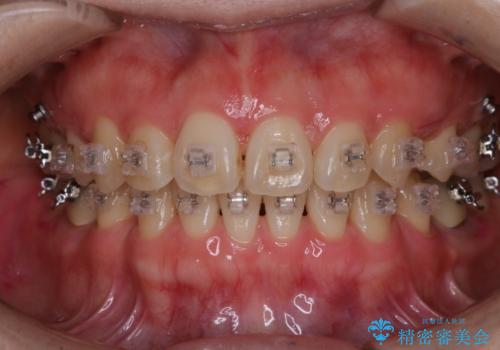

ワイヤー矯正中に歯の染め出し

- ワイヤー矯正中にクリーニンング希望とのことでした。染め出しを行い歯磨き指導とPMTC60分コースを行いました。

矯正治療中も清潔な口腔内を保つことは、とても大切です。そのため、定期的に専門的な機械・材料を使用したProfessinnalcleaning(pmtc)を行うことがおススメです。